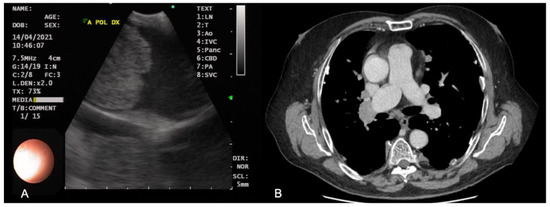

In the experience of our Interventional Pneumology Centre, the most representative case of pulmonary embolism evaluated by EBUS is shown in Figure 1.

Figure 1.

Echoendoscopic (A) and CT (B) images of pulmonary embolism of the right main pulmonary artery.